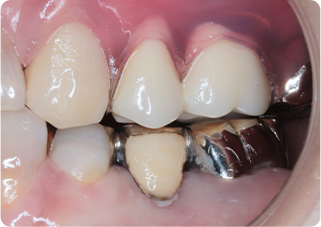

自家歯牙移植・精密根管治療・セラミッククラウン症例

術前

術後

| 主訴 | 奥歯の銀歯がぐらぐらして取れそう |

|---|---|

| 治療期間/回数 | 5ヵ月、10回 |

| 価格(税込) | 264,000円(税込) |

| リスク・副作用 | 生着不良、歯根吸収、骨性癒着の可能性 |

| ポイント | 銀歯の中でむし歯が進行し、保存不可能だったため抜歯し、後ろの親知らずを移植。移植の際に3Dプリンターで作製した親知らずのレプリカを使用し、治療時間の短縮と移植ポジションの確認を行った。生着するのを待ち、精密根管治療を行った後、セラミッククラウンを装着した。 |